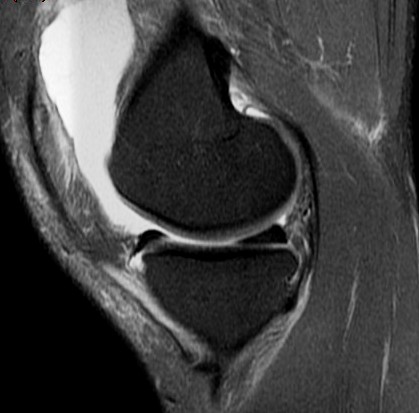

25 y/o twisting injury

Torn mid medial patellofemoral ligemnt, chondral defect of the lateral femoral condyle and medial patella. Displaced chondral fragment adjacent to the lateral femur within the lateral joint space. Also has trochlear dysplasia type B with a subtle supratrochlear spur and an increased tibial tubercle central trochlear distance.

Patellar dislocation